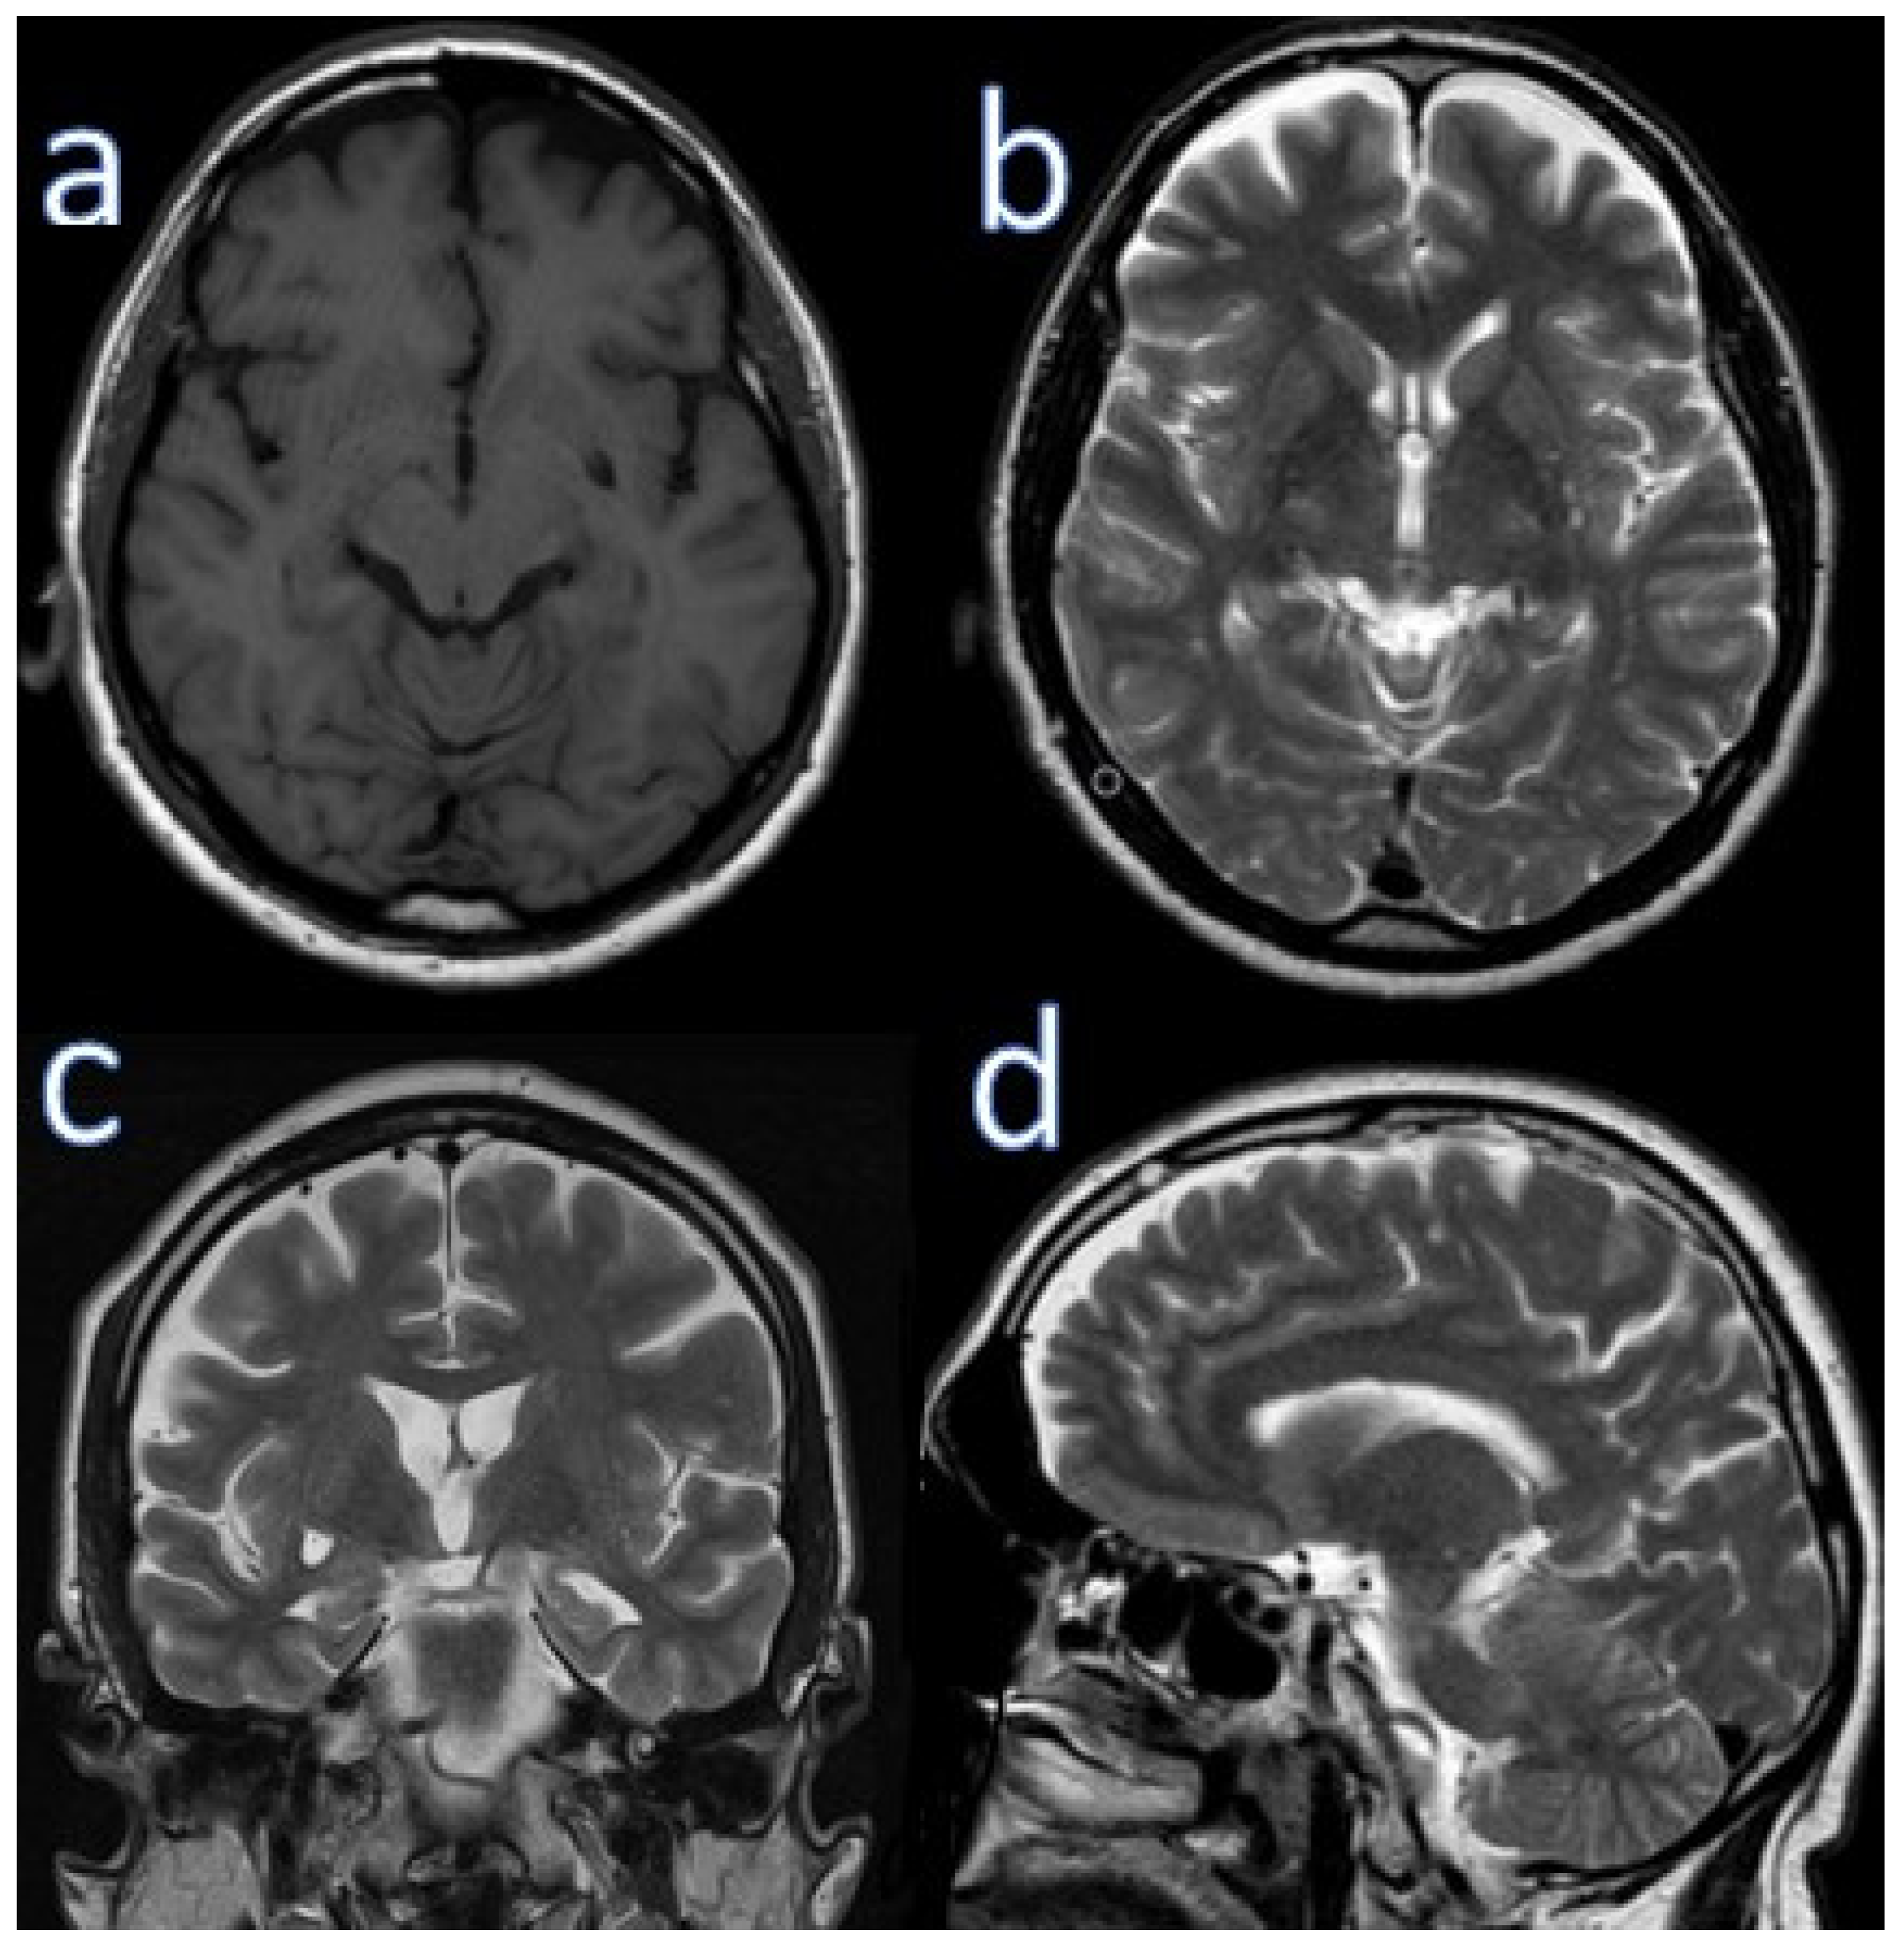

Neurological examination results were normal. He scored 20/30 on MMSE (he did not orient to time, lost 3 points when counting backwards and 3 points when recalling words after distraction), and 10/10 on the CDT. A head MR scan performed 17 months before presentation showed frontoparietal cortical atrophy, small disseminated vascular lesions up to 6 mm in the frontal and occipital lobes, and an enlarged Virchow-Robin space in the left globus pallidus (5 × 10 mm) (Figure 2).

Figure 2. Brain MRI of case 2. (a) Axial T1 weighted, (b) axial T2 weighted (upper row). (c) Coronal T2 weighted, (d) sagittal T2 weighted (lower row).

It was been shown that frontal-parietal cortical areas are involved in neuroimaging studies in AD patients more often than in patients with typical AD, but less often than in patients with bvFTD [4]. In our patients, we observed small fronto-parietal atrophy with widening of Sylvian fissure. Temporal horns dilatations and white matter hyperintensity (T2-weighted MR) were present on MR of Case 2. White matter abnormalities and frontoparietal grey matter atrophy have been observed in FTD patients, especially in GRN mutation carriers.